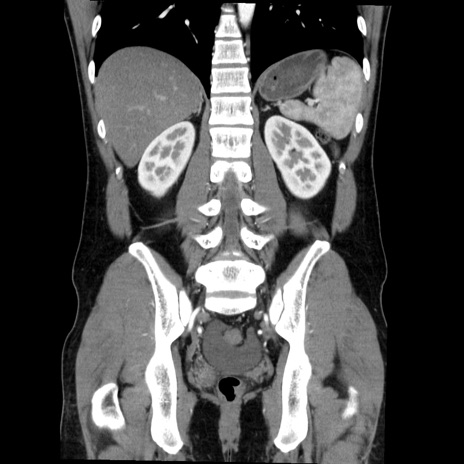

症例36(冠状断像)

【症例】20歳代 男性

【主訴】心窩部痛

【現病歴】今朝より上腹部痛あり。一旦軽快していたが再度出現したため救急要請。昨日夕に白身の魚を含む刺身を食べた。

【身体所見】BP 136/89mmHg、HR 74/min、BT 37.0℃、腹部:膨満、軟、心窩部に圧痛あり。反跳痛なし、筋性防御なし、腸雑音やや亢進あり。

【データ】WBC 17700、CRP 0.48